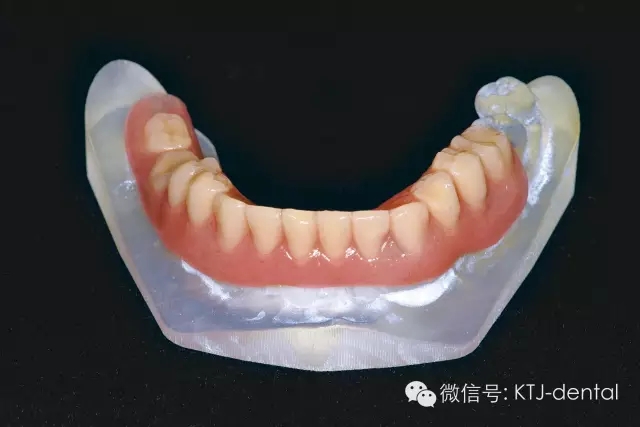

圖5 格萊美種植導板(類型為牙支持式導板)

圖6 標記有基臺位置的3D打印模型,模型用于制作即刻修復義齒及根據(jù)基臺位置預先掏空

本病案小結(jié):使用預成種植套筒冠基臺行無牙合即刻負重手術(shù)操作簡單,效果可靠,臨床應用方便快捷。但種植體的平行度是保證此修復方式成功實施的關鍵。本病例的CAD CAM手術(shù)導板在應用過程中發(fā)揮以下作用:嚴格控制種植體的平行度,避免損傷下牙槽神經(jīng)及頦神經(jīng)(無須翻瓣暴露神經(jīng)),根據(jù)種植體植入深度預選適當?shù)幕_,根據(jù)術(shù)前打印模型預先調(diào)磨即刻負重義齒。CAD CAM手術(shù)導板的應用使得手術(shù)操作有更強的預期性。在應用技巧方面,預先保留不影響植入位點的牙齒,獲得更為精確的牙支持式的手術(shù)導板,減少了手術(shù)誤差。半程導板配套的器械盒應該合理地與相應種植系統(tǒng)外科器械配合使用,并根據(jù)骨的質(zhì)地采用相應的預備方式,使得植入位點精確,并獲得良好的初期穩(wěn)定性完成下一步的即刻負重治療。